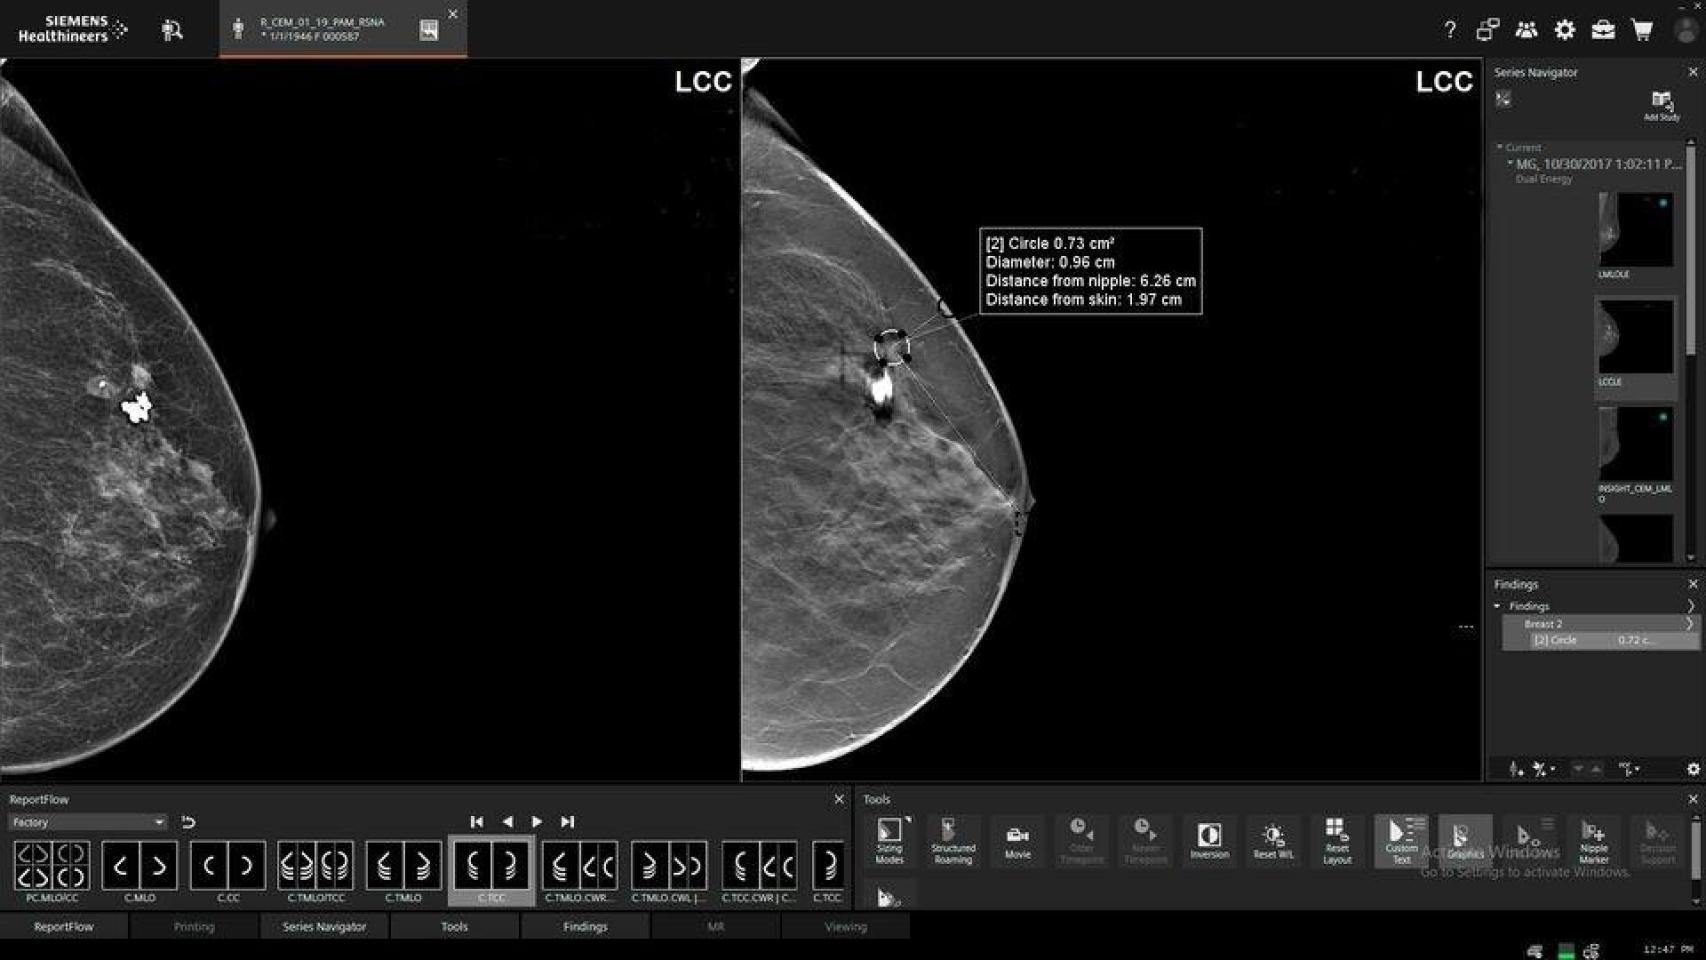

Fuentes de la Junta indican que "actualmente, cuando se realiza una mamografía a una mujer dentro del programa de cribado del cáncer de mama existen tres posibles diagnósticos: negativo, positivo y

lesión posiblemente benigna".

Los casos negativos reciben notificación; los positivos, lógicamente también para iniciar tratamiento; pero en el caso de los no concluyentes existe la posibilidad de que no se comunicase a las mujeres que "su caso sigue un procedimiento clínico con supervisión médica".